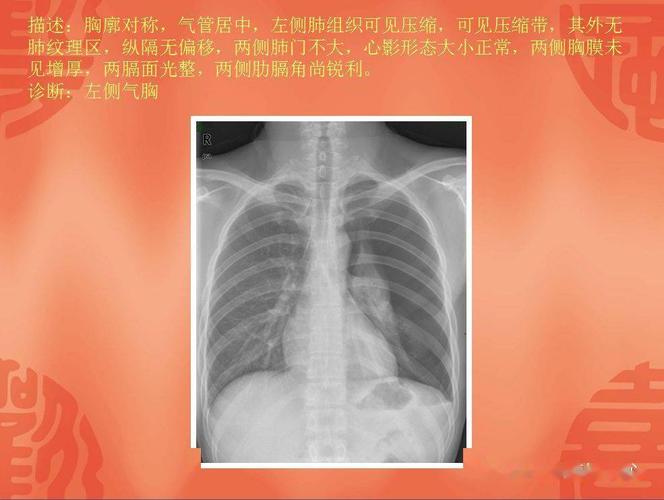

液平面x线图片,气液平面x线图片

4.17 气胸复张,右下肺见液平面已吸收

气液平面x线图片

气胸x线胸片图解